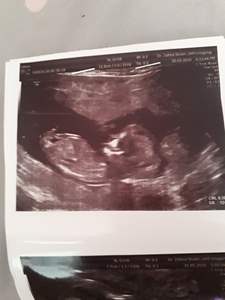

بچه ها تا حالا نظریه ناب تو تشخیص جنسیت جنین برای کسی اشتباه بوده؟!